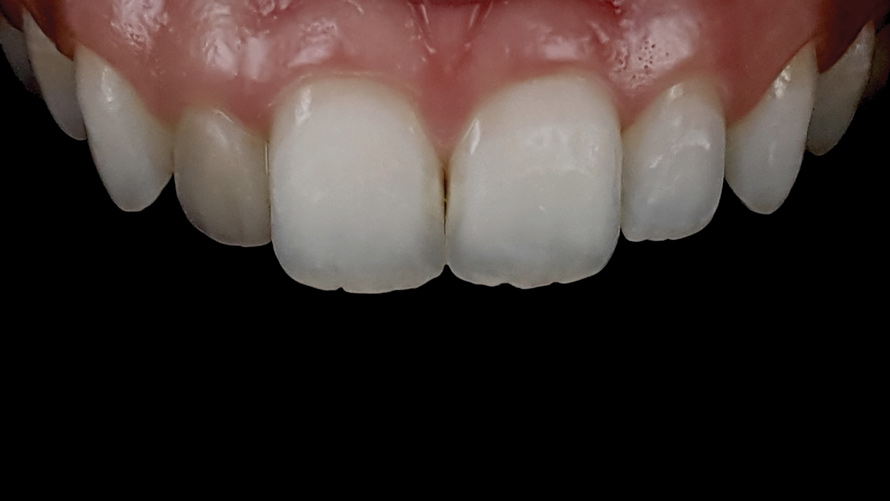

(9.) Preoperative esthetic case documentation using a smartphone and an EALS device.

Figure 9

(10.) Preoperative esthetic case documentation using a smartphone and an EALS device.

Figure 10

(11.) Preoperative esthetic case documentation using a smartphone and an EALS device.

Figure 11